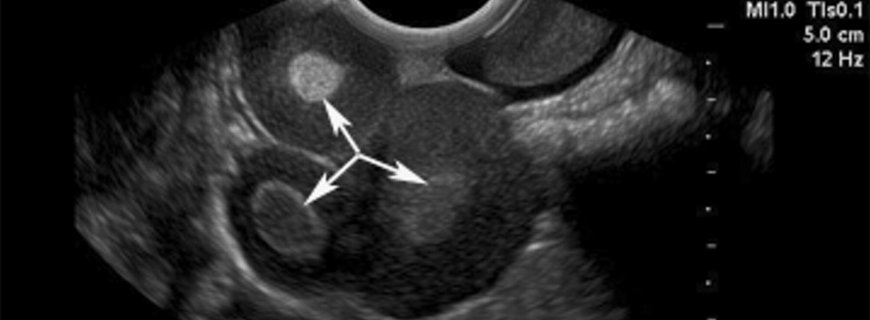

Yumurtalık kistleri yumurtalığın içinde ya da yüzeyindeki sıvı ile dolu keselerdir. Çoğu yumurtalık kisti fizyolojiktir ve genellikle belirtisiz seyreder. En sık görülen fizyolojik kistler folliküler...

Folliküler Kist Nedir ve Neden Oluşur?Folliküler kist yumurtalık dokusunda bulunan fizyolojik bir yumurtalık kistidir. Yumurtalık yüzeyinde bir köpük gibi görünen, berrak ya da saman sarısı renginde s...

Korpus Luteum Kisti Nedir?Normal bir folliküler kist yumurtalık follikülü açığa çıkardığında sonuçta oluşan yapıya korpus luteum kisti denir. Çoğu korpus luteum kisti kendiliğinden kaybolur. Bazen k...

Teka Lutein Kisti Nedir ve Neden Oluşur?Teka lutein kistleri yumurtalıkları ılımlıdan çok büyüğe kadar büyüten fizyolojik yumurtalık kistleridir. Genellikle yumurtalıkların hormonlar tarafından çok uy...